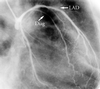

Fig. 2 Selective angiogram of the left coronary artery shows the main trunk and the left anterior descending coronary artery (LAD) displaced upward. The proximal portion of the diagonal branch (Diag) is markedly compressed by the aneurysm.